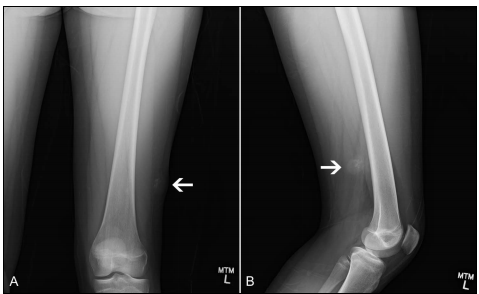

兒童膝關(guān)節(jié)周?chē)侨饬鲋w生長(zhǎng)潛能保留的外科治療進(jìn)展和未來(lái)注:本文章以“特約來(lái)稿”形式已發(fā)表在腫瘤防治研究2024年第51卷第11期摘要:隨著影像學(xué)的發(fā)展、外科技術(shù)的進(jìn)步、多藥物聯(lián)合化療以及術(shù)后肢體功能康復(fù)的密切配合,保肢后腫瘤局部復(fù)發(fā)率和患者的生存率達(dá)到了與截肢相同的臨床結(jié)果,保肢已成為現(xiàn)代肢體惡性骨腫瘤治療的流行趨勢(shì)。膝關(guān)節(jié)周?chē)?,包括股骨遠(yuǎn)端和脛骨近端,是骨肉瘤最好發(fā)的部位。瘤段截除后使用金屬假體置換替代骨缺損是保肢最常用的方法,也是患者術(shù)后迅速恢復(fù)肢體功能最可靠的保肢手段。本篇討論的主要是臨床上面臨的兒童骨肉瘤保肢技術(shù)的一個(gè)挑戰(zhàn),如何最大限度的保留兒童患肢肢體生長(zhǎng)潛能,從而減少日后雙下肢肢體不等長(zhǎng),以及由此引發(fā)的跛行步態(tài)、骨盆傾斜和脊柱側(cè)彎等并發(fā)癥,是保肢技術(shù)發(fā)展幾十年來(lái)最前沿的精準(zhǔn)醫(yī)療技術(shù)跨越之一。以?xún)和晒沁h(yuǎn)端骨肉瘤為例,肢體生長(zhǎng)潛能的保留包括兩種情況,一是犧牲膝關(guān)節(jié),這是臨床上大部分患者需要采取的手術(shù)方式。即股骨遠(yuǎn)端骨關(guān)節(jié)(包括骨骺生長(zhǎng)板)一并切除后,如何保留膝關(guān)節(jié)對(duì)側(cè)脛骨近端骨骺的生長(zhǎng)潛能。二是保留膝關(guān)節(jié),即根據(jù)股骨遠(yuǎn)端腫瘤與骨骺生長(zhǎng)板之間的距離,在保證安全切除邊界的前提下精確截骨,骨骺生長(zhǎng)板可能被切除或保留,但膝關(guān)節(jié)是保留的,重建方式相當(dāng)于“股骨干”節(jié)段重建。這種情況適用于良好化療反應(yīng)的患者,也歸功于目前興起的3D打印重建假體,這種保留膝關(guān)節(jié)的方式越來(lái)越受到青睞。本文針對(duì)兒童膝關(guān)骨肉瘤的外科治療進(jìn)展及未來(lái)發(fā)展方向進(jìn)行總結(jié),以期對(duì)骨腫瘤醫(yī)生治療該部位疾病提供一定幫助。關(guān)鍵詞:兒童骨肉瘤,保肢,生長(zhǎng)潛能,外科治療,未來(lái)發(fā)展引言骨肉瘤為罕見(jiàn)腫瘤,發(fā)病率為3~4.5個(gè)/百萬(wàn)人群,好發(fā)于青春期骨骼生長(zhǎng)速度最快的年齡段(0~9歲和10~24歲每百萬(wàn)人群分別為1.9和6.7個(gè))[1]。骨肉瘤雖然罕見(jiàn),但仍是兒童和青少年最常見(jiàn)的原發(fā)惡性骨腫瘤,最常見(jiàn)的發(fā)病部位為長(zhǎng)骨的干骺端(圖1),其中約50%的病變發(fā)生在膝關(guān)節(jié)周?chē)ü晒沁h(yuǎn)端和脛骨近端。典型的影像學(xué)表現(xiàn)為干骺端成骨性骨破壞,可侵犯或突破骨骺生長(zhǎng)板,骨外軟組織包塊形成,可見(jiàn)典型的“Codman”三角或“日光射線”現(xiàn)象。新輔助化療的開(kāi)展,使患者五年生存率由低于20%升高到60%,且90%以上的患者可以達(dá)到保肢的要求,保肢和既往截肢的局部復(fù)發(fā)率幾乎相同(<5%)[2]。保肢不僅保留了患者的肢體,最大的優(yōu)點(diǎn)還在于保證了患者的心理健康。隨著影像學(xué)和外科技術(shù)的飛速發(fā)展,保肢也進(jìn)入了精準(zhǔn)醫(yī)療的發(fā)展軌道。兒童保肢的實(shí)施理念不同于成人,成人骨骺已閉合,肢體不再生長(zhǎng),術(shù)后不存在肢體不等長(zhǎng)問(wèn)題,但對(duì)于兒童,其處理原則和手術(shù)方法具有其獨(dú)特性。AB圖1典型兒童股骨遠(yuǎn)端骨肉瘤,可見(jiàn)成骨性破壞,骨外軟組織包塊,“日光射線”現(xiàn)象,腫瘤侵犯骨骺生長(zhǎng)板(A);典型兒童脛骨近端骨肉瘤,成骨性破壞,“Codman三角”形成,腫瘤未突破骨骺生長(zhǎng)板(B)兒童骨肉瘤術(shù)前肢體生長(zhǎng)潛能評(píng)估女孩骨骼生長(zhǎng)最快的時(shí)期是12~14歲,男孩是14~16歲。正常下肢的長(zhǎng)度70%依賴(lài)膝關(guān)節(jié)周?chē)趋康纳L(zhǎng)(股骨遠(yuǎn)端占40%,脛骨近端30%),而股骨近端和脛骨遠(yuǎn)端骨骺各占15%[3]。舉例說(shuō)明,一個(gè)10歲男孩的股骨遠(yuǎn)端骨肉瘤切除后,由于股骨遠(yuǎn)端骨骺每年生長(zhǎng)1.6cm,到16歲停止生長(zhǎng)時(shí),患肢比對(duì)側(cè)將短縮9.6cm。第一次手術(shù)計(jì)劃時(shí),術(shù)中可以將患側(cè)股骨假體比對(duì)側(cè)股骨有意延長(zhǎng)2cm,還是相差7cm左右。由于雙側(cè)肢體相差2cm之內(nèi),可以通過(guò)墊高鞋墊來(lái)改善步態(tài),因此對(duì)于患者延長(zhǎng)5~6cm即可滿(mǎn)足日后生活需求。對(duì)于14歲的股骨遠(yuǎn)端男孩,到16歲停止生長(zhǎng),通過(guò)術(shù)中延長(zhǎng)2cm的假體調(diào)節(jié),骨骼成熟停止生長(zhǎng)后可以達(dá)到肢體等長(zhǎng),因此患者可以使用成人假體,減少日后需要將兒童假體更換為成人假體的手術(shù)可能。對(duì)于10歲之前的患者,由于尚未達(dá)到青春肢體快速增長(zhǎng)期,肢體短縮差距預(yù)測(cè)準(zhǔn)確性低,可以暫且采取術(shù)中最大限度延長(zhǎng)肢體的方法(2~3cm),腫瘤安全期過(guò)后再行肢體延長(zhǎng)手術(shù)。手術(shù)計(jì)劃膝關(guān)節(jié)周?chē)侨饬?,在新輔助化療后影像學(xué)一方面評(píng)估腫瘤的化療反應(yīng)及保肢的可行性,另一方面評(píng)估腫瘤與骨骺生長(zhǎng)板的關(guān)系(圖2)[4]。以股骨遠(yuǎn)端骨肉瘤為例,在遵循腫瘤廣泛切除原則的基礎(chǔ)上,股骨遠(yuǎn)端骨骺大多數(shù)情況下需要與腫瘤一并切除(typeII和III),如何保留脛骨近端的骨骺的生長(zhǎng)潛能是本文討論的第一個(gè)重要內(nèi)容。少數(shù)情況下對(duì)于化療反應(yīng)良好的患者,根據(jù)腫瘤與股骨遠(yuǎn)端骨骺生長(zhǎng)板的距離,在達(dá)到腫瘤廣泛切除的目的同時(shí),存在可以保留此生長(zhǎng)板的可能(typeI)。當(dāng)然也有可能通過(guò)生長(zhǎng)板或在生長(zhǎng)板的遠(yuǎn)側(cè)截骨,但無(wú)論生長(zhǎng)板是否保留,患者的膝關(guān)節(jié)是保留的,重建中心轉(zhuǎn)變?yōu)橹羞h(yuǎn)段股骨干重建(typeII)。這是本文討論的第二個(gè)重要內(nèi)容。I型(TypeI)II型(TypeII)III型(TypeIII)圖2根據(jù)腫瘤邊界距離骺板及關(guān)節(jié)面的距離進(jìn)行分型,I型(TypeI)腫瘤與骺板尚有一定的安全距離,截骨后骺板可以保留。II型(TypeII)腫瘤臨近骺板,可以經(jīng)骺板或骺板下截骨或關(guān)節(jié)內(nèi)切除。III型(TypeIII),腫瘤穿透骺板,關(guān)節(jié)面無(wú)法保留,關(guān)節(jié)內(nèi)切除由于股骨遠(yuǎn)端骨骺的消失,孩子年齡越輕,日后雙下肢不等長(zhǎng)(limblengthdiscrepancy,LLD)的程度越明顯,進(jìn)而出現(xiàn)跛行步態(tài)加重、骨盆傾斜和脊柱側(cè)彎(圖3)等并發(fā)癥[5]。圖3女孩,6歲,股骨遠(yuǎn)端骨肉瘤切除,假體置換術(shù)后5年,患側(cè)股骨短縮,雙側(cè)肢體不等長(zhǎng),繼發(fā)骨盆傾斜瘤段截除后骨缺損重建方法瘤段截除后,骨缺損修復(fù)的方法多種多樣,包括生物學(xué)和非生物學(xué)重建方法,前者包括如瘤骨滅活再植、大段異體骨關(guān)節(jié)移植、骨搬運(yùn)、關(guān)節(jié)融合等,后者為腫瘤假體置換,是目前保肢最常用的方式。3D打印技術(shù)在腫瘤切除后骨缺損重建方面的應(yīng)用越來(lái)越廣泛。本文將對(duì)目前臨床中常用的手術(shù)重建方式進(jìn)行梳理、總結(jié),以期能為骨腫瘤醫(yī)生治療該部位疾病提供一定幫助,為將來(lái)的創(chuàng)新發(fā)展提供啟示。1、犧牲膝關(guān)節(jié)的骨關(guān)節(jié)切除重建因腫瘤侵犯骨骺或與骨骺距離太近,為了達(dá)到安全邊界,腫瘤連同骨骺、關(guān)節(jié)連接結(jié)構(gòu)一并切除,這是臨床上最常見(jiàn)的情況(typeII和III)。為了盡量保留膝關(guān)節(jié)對(duì)側(cè)骨骺板生長(zhǎng)潛能,可進(jìn)行以下重建方案。1.1瘤殼滅活再植或異體骨關(guān)節(jié)移植這兩種方法是2000年前臨床常用的方法,那時(shí)的腫瘤假體在國(guó)內(nèi)剛剛起步,還是定制假體,生產(chǎn)廠家很少,制作時(shí)間長(zhǎng),無(wú)法滿(mǎn)足臨床需求。主要操作步驟為,標(biāo)本離體,清理掉腫瘤組織,使用高滲鹽水或液氮進(jìn)行瘤骨滅活,原位回植到缺損部位,并使用鋼板或髓內(nèi)釘進(jìn)行固定(圖4)。自體瘤骨無(wú)需購(gòu)買(mǎi),且匹配度完美,術(shù)后排異反應(yīng)和感染的發(fā)生率低,因此在當(dāng)時(shí)那個(gè)年代應(yīng)用較多,但缺點(diǎn)也很明顯,局部腫瘤滅活可能不徹底,有增加局部復(fù)發(fā)的風(fēng)險(xiǎn),術(shù)后化療也會(huì)影響骨的愈合,有骨折風(fēng)險(xiǎn)。異體骨關(guān)節(jié)多為成人骨骼,與兒童骨匹配度較差,術(shù)后存在排異、感染、不愈合、骨折等并發(fā)癥(圖5)。上述兩種方法均保留了膝關(guān)節(jié)對(duì)側(cè)正常骨骺的生長(zhǎng)潛能,盡管術(shù)后需要長(zhǎng)時(shí)間佩戴膝關(guān)節(jié)支具,但均存在膝關(guān)節(jié)不穩(wěn)或脫位的并發(fā)癥,這兩種方法已基本擯棄不用。圖4股骨遠(yuǎn)端骨肉瘤瘤殼滅活再植圖5脛骨近端骨肉瘤異體骨關(guān)節(jié)移植1.2發(fā)展中的兒童關(guān)節(jié)假體重建1.2.1半關(guān)節(jié)假體鑒于上述滅活瘤骨骨殼和異體半關(guān)節(jié)移植的不足,使用半關(guān)節(jié)假體替代骨缺損在2000年后使用逐步增多[6-8]。半關(guān)節(jié)假體為定制型,缺損段和假體柄一體化,假體柄為骨水泥固定。雖然仍然出現(xiàn)膝關(guān)節(jié)不穩(wěn),但由于兒童體重輕,適應(yīng)能力強(qiáng),很多患者獲得了良好的術(shù)后功能,且很多患者使用超過(guò)十年(圖6),當(dāng)然顯而易見(jiàn)的缺點(diǎn)是一體化的假體日后翻修困難。近幾年的發(fā)展一是將假體缺損段改為組配型,有利于安裝拆卸,假體柄也有非骨水泥固定柄可選擇。二是為減少膝關(guān)節(jié)不穩(wěn)的發(fā)生,改善通過(guò)精心設(shè)計(jì)假體長(zhǎng)度及關(guān)節(jié)面大小,術(shù)中盡量保留關(guān)節(jié)周?chē)g帶組織,使用LARS韌帶重建關(guān)節(jié)周?chē)g帶(圖7),或穿過(guò)假體上預(yù)制的孔道及關(guān)節(jié)對(duì)側(cè)骨上的開(kāi)通孔道重建交叉韌帶,并重建側(cè)副韌帶[7,8]。經(jīng)過(guò)這些改進(jìn),膝關(guān)節(jié)穩(wěn)定性進(jìn)一步加強(qiáng),半數(shù)以上的患者可達(dá)到滿(mǎn)意的功能評(píng)分[8,9]。三是將半關(guān)節(jié)改進(jìn)為兒童鉸鏈型假體,增加膝關(guān)節(jié)穩(wěn)定性(如下)。圖6股骨遠(yuǎn)端兒童半關(guān)節(jié)假體,置換術(shù)后10年復(fù)查,患者行走功能基本正常,假體無(wú)松動(dòng)跡象。AB圖7股骨遠(yuǎn)端半關(guān)節(jié)假體,假體采用組配可延長(zhǎng)設(shè)計(jì),使用LARS韌帶重建關(guān)節(jié)周?chē)g帶(A),重建術(shù)后片(B)1.2.2兒童鉸鏈型膝關(guān)節(jié)假體(股骨遠(yuǎn)端或脛骨近端)上述半關(guān)節(jié)假體雖然經(jīng)過(guò)改進(jìn),患者仍有不同程度的膝關(guān)節(jié)不穩(wěn)和膝關(guān)節(jié)脫位的發(fā)生,且術(shù)后患者需要長(zhǎng)時(shí)間外支具固定。為解決這個(gè)問(wèn)題,國(guó)內(nèi)自2015年開(kāi)始設(shè)計(jì)應(yīng)用兒童股骨遠(yuǎn)端鉸鏈膝關(guān)節(jié)假體[5]。假體為組配式,股骨柄采用水泥固定或生物固定于股骨髓腔,其設(shè)計(jì)理念不同于成人鉸鏈膝關(guān)節(jié)假體的部位在于脛骨側(cè),脛骨側(cè)平臺(tái)骨質(zhì)不切除,且不進(jìn)行脛骨近端髓腔處理。將8~10mm的簡(jiǎn)易“T”型脛骨假體的假體柄穿過(guò)脛骨骨骺進(jìn)入髓腔內(nèi),同時(shí)兩側(cè)各有一個(gè)防旋轉(zhuǎn)針(圖8)。我們2021年報(bào)道了34例兒童股骨遠(yuǎn)端骨肉瘤患者接受了此假體重建,平均隨訪2.8年,膝關(guān)節(jié)穩(wěn)定,患者可進(jìn)行日常生活、慢跑、騎自行車(chē)等,術(shù)后膝關(guān)節(jié)屈曲角度為100°~130°,術(shù)后平均MSTS93評(píng)分為26.7[5]。AB圖8特制股骨遠(yuǎn)端兒童型關(guān)節(jié)假體照片(A),術(shù)后1年復(fù)查雙下肢X線片(B)雙側(cè)脛骨長(zhǎng)度基本相同,提示脛骨近端骨骺生長(zhǎng)潛能得以保留脛骨近端兒童型假體與股骨遠(yuǎn)端假體類(lèi)似,目的也是增強(qiáng)脛骨近端兒童假體置換后膝關(guān)節(jié)穩(wěn)定,并盡量減少對(duì)膝關(guān)節(jié)對(duì)側(cè)股骨遠(yuǎn)端骨骺生長(zhǎng)潛能的影響(圖9)。與上述股骨遠(yuǎn)端兒童鉸鏈假體的設(shè)計(jì)理念一樣,簡(jiǎn)易“T”型股骨側(cè)假體也是盡量減少對(duì)股骨側(cè)骨骺的影響。假體柄采用一光滑細(xì)柄,直徑8~10mm,長(zhǎng)度100mm,股骨柄外翻5°。股骨側(cè)無(wú)需截骨,確定好髓腔位置后,直接將股骨假體柄打入。該假體于2019年臨床設(shè)計(jì)使用,術(shù)后短期臨床效果滿(mǎn)意,患者正處在隨訪階段。AB圖9脛骨近端兒童型鉸鏈假體(A),術(shù)后一年復(fù)查雙下肢全長(zhǎng)X線片顯示雙側(cè)股骨生長(zhǎng)長(zhǎng)度相同(B)盡管經(jīng)歷了上述滅活再植/異體骨關(guān)節(jié)移植到人工半關(guān)節(jié)假體,再到近期的兒童鉸鏈型膝關(guān)節(jié)假體,腫瘤治療安全性和膝關(guān)節(jié)穩(wěn)定性得到了逐步加強(qiáng),假體設(shè)計(jì)也由定制一體化向組配式發(fā)展,假體柄的固定方式也由單純骨水泥固定發(fā)展為有生物型固定柄可以選擇。膝關(guān)節(jié)對(duì)側(cè)的骨骺生長(zhǎng)潛能保留可以達(dá)到74.3-87.5%[5,20]。如何完全消除對(duì)對(duì)側(cè)骨骺的影響,還需要進(jìn)一步研究.2.保留關(guān)節(jié)的瘤段切除股骨遠(yuǎn)端或脛骨近端骨肉瘤,少數(shù)情況下腫瘤距離骨骺生長(zhǎng)板或關(guān)節(jié)面尚有一定的距離(typeI和II),在患者化療反應(yīng)良好的前提下,可以考慮保留關(guān)節(jié)的瘤段切除手術(shù)(Joint-preservationsurgery,JPS)。重建也就類(lèi)似于股骨干節(jié)段重建技術(shù)[10]。對(duì)于typeII,在化療反應(yīng)良好的患者中,有人嘗試了更大膽的做法,經(jīng)骨骺生長(zhǎng)板截骨(如下)。以股骨遠(yuǎn)端骨肉瘤為例,根據(jù)核磁T1加權(quán)像圖像上腫瘤邊界距離骺板及關(guān)節(jié)面的距離[11],保留關(guān)節(jié)的截骨分為三類(lèi)(圖2):①經(jīng)干骺端截骨(腫瘤邊界距離骺板≥10mm),骺板保留;②經(jīng)骺板截骨(腫瘤臨近骺板,截骨邊界距離關(guān)節(jié)面≥10mm);③骺板下截骨(腫瘤侵犯部分骺板,截骨邊界距離關(guān)節(jié)面≥10mm)[12]。膝關(guān)節(jié)保留更能提供良好的肢體功能。第②和③截骨情況在目前3D導(dǎo)板精準(zhǔn)截骨和打印假體興起的情況下,越來(lái)越受到骨腫瘤科醫(yī)師的青睞。保留關(guān)節(jié)的方法優(yōu)勢(shì)非常明顯,但對(duì)于選取第②和③截骨方式需要非常慎重,畢竟增加了局部腫瘤復(fù)發(fā)的風(fēng)險(xiǎn)。因?yàn)閷?duì)于骺板是否是阻擋骨肉瘤侵犯的屏障,研究早有定論。影像學(xué)上發(fā)現(xiàn)骺板侵犯的比例占44%,而術(shù)后病理顯示穿透骺板的比例超過(guò)80%[13]。因此這種截骨方式選擇需要考慮多個(gè)因素,包括腫瘤的大小、位置、病理類(lèi)型、患者的年齡、骨骺的生長(zhǎng)情況以及醫(yī)療團(tuán)隊(duì)的經(jīng)驗(yàn)等。其適應(yīng)證包括:①腫瘤對(duì)新輔助化療有良好的反應(yīng),這是最重要的前提條件,表現(xiàn)為X光平顯示大量硬化改變或邊緣良好的腫瘤,磁共振成像(MRI)顯示骨外腫瘤明顯縮小,血管造影未見(jiàn)腫瘤顯色,或鉈201(201TI)灌注造影檢查未見(jiàn)腫瘤內(nèi)顯影[14];②可以達(dá)到精準(zhǔn)截骨的要求,保留遠(yuǎn)端關(guān)節(jié)面長(zhǎng)度>1cm;③腫瘤安全切緣≥10mm;④無(wú)遠(yuǎn)處轉(zhuǎn)移(EnnekingIIA期、IIB期)或存在可切除的遠(yuǎn)處轉(zhuǎn)移病灶(EnnekingIII期)。Bellanova等2013年在個(gè)體化特異3D打印導(dǎo)板指導(dǎo)下精確截骨,4例膝關(guān)節(jié)周?chē)侨饬龅那谐吔缇鶠殛幮訹15]。Wong等[16]2013年報(bào)道5例膝關(guān)節(jié)骨肉瘤導(dǎo)航引導(dǎo)下骺板下精確切割保留關(guān)節(jié)面,雖然切割線距離腫瘤僅2mm左右,但平均隨訪41個(gè)月無(wú)一例復(fù)發(fā),平均MSTS評(píng)分平均為29分,保留的關(guān)節(jié)面無(wú)一例出現(xiàn)缺血性壞死。雖然Andreou等在尋找骨肉瘤局部復(fù)發(fā)的危險(xiǎn)性因素的研究中,他們發(fā)現(xiàn)在1355個(gè)骨肉瘤中有123個(gè)切緣非常臨近腫瘤,但這并不是腫瘤局部復(fù)發(fā)的危險(xiǎn)因素[17]。然而對(duì)于保留關(guān)節(jié)面的手術(shù),過(guò)于緊靠腫瘤邊界的截骨線仍存在腫瘤長(zhǎng)期安全性的擔(dān)憂(yōu)2.1經(jīng)干骺端截骨保留骨骺生長(zhǎng)板的缺損重建兩種重建方法,一是使用滅活瘤骨或異體骨聯(lián)合自體腓骨移植重建不失為一種較理想的生物學(xué)重建方法(圖10),二是3D打印中段假體重建(圖11)。插入到滅活瘤骨或異體骨骨髓腔的自體腓骨有良好的再生、塑形能力。該結(jié)構(gòu)依靠鋼板、螺釘給予滅活瘤骨或異體骨提供早期支撐,依靠自體腓骨塑形增粗、與滅活瘤骨或異體骨融合提供遠(yuǎn)期支撐。其中,較游離腓骨移植來(lái)說(shuō),帶血管蒂的自體腓骨移植重建可能有更加明顯的促骨愈合作用,但仍需長(zhǎng)期隨訪驗(yàn)證。圖1012歲男孩,股骨遠(yuǎn)端骨肉瘤,新輔助治療后行瘤段截除(保留骨骺)、滅活瘤骨、聯(lián)合自體腓骨移植重建缺損,術(shù)后2年無(wú)腫瘤復(fù)發(fā),骨骺生長(zhǎng)潛能保留,雙側(cè)肢體等長(zhǎng)圖11.10歲女孩,右股骨遠(yuǎn)端骨肉瘤,干骺端截骨,保留骨骺生長(zhǎng)板,3D打印假體重建,一年后復(fù)查2.2經(jīng)骨骺生長(zhǎng)板或生長(zhǎng)板下截骨的缺損重建現(xiàn)代影像學(xué)、導(dǎo)航技術(shù)以及3D打印技術(shù)的出現(xiàn),骺板或骺板下截骨保留關(guān)節(jié)面的“極限”保肢技術(shù)在臨床上得到了青睞(圖12)。術(shù)前根據(jù)影像學(xué)資料,規(guī)劃、設(shè)計(jì)的3D打印定制假體匹配度好、機(jī)械強(qiáng)度高,多孔結(jié)構(gòu)可達(dá)到骨長(zhǎng)入的效果。隨著近些年3D打印技術(shù)的發(fā)展,定制假體的制造周期縮短、生產(chǎn)成本下降,技術(shù)逐漸成熟。但要術(shù)前根據(jù)影像學(xué)資料詳細(xì)規(guī)劃截骨位置,可使用定制3D截骨導(dǎo)板精確截骨[19]。3D打印技術(shù)的出現(xiàn)解決了人工假體與干骺端的長(zhǎng)期穩(wěn)定連接及融合的難題。首先,3D打印技術(shù)可以制備處大小、形狀與缺損完全匹配的假體;此外,該技術(shù)可以通過(guò)打印多孔金屬小梁結(jié)構(gòu),隨著骨長(zhǎng)入的實(shí)現(xiàn),達(dá)到長(zhǎng)期、永久的固定效果。遠(yuǎn)期的假體松動(dòng)和感染等并發(fā)癥還需要長(zhǎng)期的隨訪觀察。AB圖12、8歲男孩,右股骨遠(yuǎn)端骨肉瘤經(jīng)骺板截骨,3D打印假體置換(A),術(shù)后2年復(fù)查,骨骺存活并生長(zhǎng)(B)3骨搬運(yùn)Tsuchiya等描述了三種類(lèi)型的骨搬運(yùn),但骨搬運(yùn)主要應(yīng)用于四肢中段骨缺損,晚期愈合后達(dá)到生物重建的效果,且遠(yuǎn)期并發(fā)癥較少[18]。但存在針道感染、骨骺損傷、局部復(fù)發(fā)、骨折、延遲愈合、骨溶解、延遲愈合、下地時(shí)間延長(zhǎng)等。骨腫瘤切除導(dǎo)致的骨缺損,一方面由于缺損較大,另一方面病變多數(shù)靠近干骺端,腫瘤切除骺殘留骨很難進(jìn)行牢固固定,失敗率比較高。此外,由于兒童骨肉瘤患者,大多數(shù)要進(jìn)行術(shù)后輔助化療,對(duì)骨愈合有一定影響,延長(zhǎng)了骨愈合的時(shí)間。在保留關(guān)節(jié)面的手術(shù)中使用難度極大,成功率不高,文獻(xiàn)中僅為個(gè)案報(bào)道。肢體不等長(zhǎng)的處理方法1.增高鞋(墊)的使用一般作為初次腫瘤切除后2年內(nèi)的選擇[20]。LLD小于2.2cm時(shí)可由骨盆傾斜代償[21],患者通常步態(tài)正常。當(dāng)LLD繼續(xù)增大時(shí),可定制增高鞋進(jìn)行“外源性”矯正,但隔一段時(shí)間就需要調(diào)整增高鞋墊(圖13)來(lái)匹配LLD,達(dá)到步態(tài)正常的效果。圖13定制增高鞋2.“追隨”對(duì)側(cè)肢體生長(zhǎng)速度的可延長(zhǎng)關(guān)節(jié)假體可延長(zhǎng)假體的設(shè)計(jì)理念是術(shù)后定期多次延長(zhǎng)假體,達(dá)到和對(duì)側(cè)肢體相同的“生長(zhǎng)”速度,是解決LDD的一個(gè)的策略,適用于預(yù)計(jì)術(shù)后下肢短縮將超過(guò)3cm的患者(圖14),但較高的傷口并發(fā)癥和假體周?chē)腥韭适俏墨I(xiàn)較多報(bào)道的可延長(zhǎng)假體并發(fā)癥[22-26]??裳娱L(zhǎng)假體經(jīng)歷了有創(chuàng)、微創(chuàng)、無(wú)創(chuàng)的發(fā)展,最早于1976年開(kāi)始應(yīng)用[27]。第一代的可延長(zhǎng)假體代表是英國(guó)生產(chǎn)的SEER(Stanmoreextensibleendoprostheticreplacement)假體,第二代假體為組配式假體,其代表為HMRS(HowmedicaModularResectionSystem)假體。后來(lái)設(shè)計(jì)的自動(dòng)可延長(zhǎng)假體,其作用機(jī)制是膝關(guān)節(jié)屈曲運(yùn)動(dòng)帶動(dòng)棘輪機(jī)構(gòu),通過(guò)螺桿來(lái)延長(zhǎng)假體。隨后出現(xiàn)了Phenix無(wú)創(chuàng)可延長(zhǎng)假體,經(jīng)多次改進(jìn),現(xiàn)為Repiphysis假體,此假體可應(yīng)用體外磁場(chǎng)來(lái)延長(zhǎng)假體。大多數(shù)可延長(zhǎng)假體都是定制的,制造技術(shù)和延長(zhǎng)機(jī)制導(dǎo)致假體具有最小長(zhǎng)度的限制,比如延長(zhǎng)量為50mm的Stanmore假體的最小基本長(zhǎng)度為190mm(組配假體)或177mm(定制假體)。如果切除的骨不夠長(zhǎng),無(wú)法使用可延長(zhǎng)假體,要安裝這種可延長(zhǎng)假體,必須犧牲更長(zhǎng)的股骨或脛骨。對(duì)于有創(chuàng)延長(zhǎng)假體的應(yīng)用,需進(jìn)行多次切開(kāi)手術(shù)操作,感染發(fā)生率增高。既往研究中,所報(bào)道的并發(fā)癥包括無(wú)菌性松動(dòng)、假體折斷或深部感染等,假體翻修率高達(dá)22%~83%[3,22,23,27-29]。無(wú)創(chuàng)可延長(zhǎng)假體并發(fā)癥的發(fā)生率仍然很高[24,30],且只能使用骨水泥固定假體柄,因?yàn)樯锕潭〞r(shí)的劇烈打壓操作可能會(huì)損害延長(zhǎng)裝置。同時(shí),使用電磁機(jī)制的無(wú)創(chuàng)可延長(zhǎng)假體的患者術(shù)后無(wú)法進(jìn)行核磁檢查,影響術(shù)后腫瘤學(xué)評(píng)估。另一方面,可延長(zhǎng)假體價(jià)格相對(duì)昂貴,部分患者難以承受,國(guó)內(nèi)應(yīng)用較少;且由于較高的并發(fā)癥發(fā)生率,許多兒童患者在接受可延長(zhǎng)假體重建后由于各種原因,比如局部復(fù)發(fā)、遠(yuǎn)處轉(zhuǎn)移、傷口感染等,約半數(shù)的患者并沒(méi)有實(shí)現(xiàn)肢體延長(zhǎng)的最終結(jié)果。圖149歲女孩股骨遠(yuǎn)端骨肉瘤可延長(zhǎng)假體置換,術(shù)后兩年定期延長(zhǎng)假體3cm3.傳統(tǒng)組配型假體需多次切開(kāi)手術(shù)更換假體延長(zhǎng)段解決LLD(圖15)。手術(shù)要求將原切口切開(kāi),脫位膝關(guān)節(jié)假體,切除假體周?chē):?,充分松解,股骨遠(yuǎn)端假體可以達(dá)到延長(zhǎng)2cm,脛骨近端假體可以達(dá)到延長(zhǎng)1cm的結(jié)果??梢远啻问中g(shù)延長(zhǎng),但有增加假體周?chē)腥镜娘L(fēng)險(xiǎn)。ABCD圖156歲女孩股骨遠(yuǎn)端骨肉瘤兒童鉸鏈假體置換,5年后雙下肢不等長(zhǎng)6cm,進(jìn)行肢體延長(zhǎng)手術(shù),術(shù)中更換組配假體延長(zhǎng)段,延長(zhǎng)2cm。術(shù)前及術(shù)后大體照片(A、B)及X線片(C、D)4.骨延長(zhǎng)對(duì)于腫瘤切除后,術(shù)后遠(yuǎn)期出現(xiàn)LLD的患者,由于假體重建存在髓內(nèi)固定柄的影響,對(duì)外固定架的置釘有影響,通常需要在對(duì)側(cè)非缺損長(zhǎng)骨進(jìn)行延長(zhǎng),如脛骨上段腫瘤進(jìn)行股骨延長(zhǎng)(圖16)。由于患者術(shù)后肢體發(fā)育及肌肉狀況較健側(cè)差,術(shù)前需要詳細(xì)評(píng)估骨質(zhì)條件,避免延長(zhǎng)過(guò)程中出現(xiàn)鋼釘松動(dòng)、延長(zhǎng)失效問(wèn)題。圖16.12歲男性脛骨近端骨肉瘤半關(guān)節(jié)假體置換,6年后雙下肢不等長(zhǎng)7cm,進(jìn)行同側(cè)肢體股骨外固定架延長(zhǎng)至雙下肢基本等長(zhǎng)3.5.對(duì)側(cè)骨骺固定術(shù)是解決LLD的另一選擇,然而,這種方法很少用于小兒膝關(guān)節(jié)周?chē)侨饬?,這會(huì)導(dǎo)致患者整體身高的損失。為使健側(cè)下肢減少生長(zhǎng)長(zhǎng)度,減小LLD的程度,手術(shù)需要對(duì)健側(cè)股骨進(jìn)行手術(shù),盡管創(chuàng)傷較小,多數(shù)患者及家屬難以接受。未來(lái)發(fā)展方向兒童膝關(guān)節(jié)周?chē)侨饬龅谋V^成人復(fù)雜且困難,其治療正處于轉(zhuǎn)型升級(jí)的關(guān)鍵階段,肢體生長(zhǎng)潛能的保留已成為治療中的重要目標(biāo)。未來(lái)的治療策略需要依賴(lài)于技術(shù)創(chuàng)新和跨學(xué)科合作,以實(shí)現(xiàn)患者的長(zhǎng)期生存和生活質(zhì)量的雙重提升。一是機(jī)器人輔助腫瘤切除更精準(zhǔn),保留骺板生長(zhǎng)能力,減少不等長(zhǎng),保留關(guān)節(jié)面,提高膝關(guān)節(jié)功能。二是無(wú)創(chuàng)可延長(zhǎng)假體的設(shè)計(jì)和發(fā)展,仍是減少患者多次手術(shù)創(chuàng)傷和假體感染風(fēng)險(xiǎn),減少肢體不等長(zhǎng)的方向。三是未來(lái)3D打印假體的發(fā)展應(yīng)結(jié)合考慮應(yīng)用生物材料和組織工程技術(shù)的發(fā)展,已有大量關(guān)于具備生物活性的組織工程支架材料的基礎(chǔ)、臨床前研究,具備復(fù)合功能的組織工程材料是未來(lái)的研究方向,目標(biāo)材料早期有提供初期強(qiáng)度的功能,并發(fā)揮抗腫瘤作用,隨后發(fā)揮其生物活性促進(jìn)骨長(zhǎng)入的作用,后期支架材料緩慢降解,新生骨完全占據(jù)骨缺損,達(dá)到長(zhǎng)久的固定。